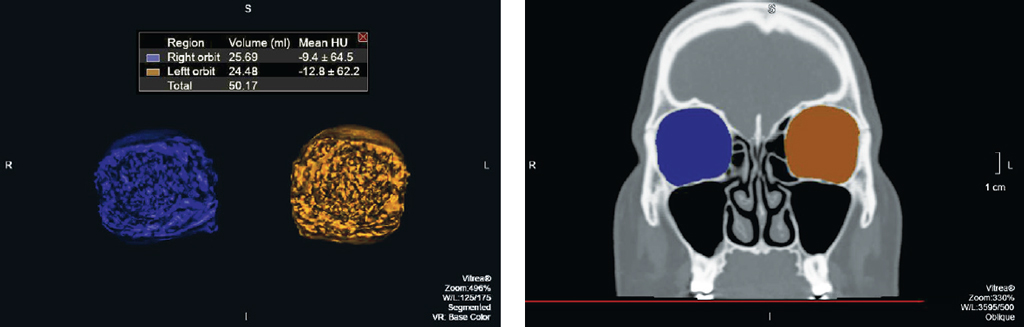

На каждом аксиальном срезе проводили маркировку всех костных границ орбит, начиная с верхней стенки до уровня дна орбиты с представлением объёмов орбит в миллилитрах. Для точности измерения чётко соблюдали костные границы и учитывали анатомические вариации строения обеих орбит (по методике расчёта объёмов орбит ранее был получен патент РФ «Способ оценки эффективности реконструктивной операции на орбите» RU2638623 C1, 14.12.2017. Бюл. № 35) (рис. 1).

Рис. 1. Мультиспиральная компьютерная томография. Обработка изображений для измерения объёмов орбиты: a — аксиальный срез, режим костного окна, маркировка костных границ обеих орбит; b — корональная реконструкция, режим костного окна, маркировка костных границ обеих орбит; c — 3D-реконструкция, объёмы правой и левой орбиты в математических единицах (мл)

Fig. 1. MSCT. Image processing for orbital volume measurement: a — axial section, bone window mode, marking of the orbital bone contours; b — coronal reconstruction, bone window mode, marking of the orbital bone contours; c — 3D-reconstruction, volumes of the right and left orbits in mathematical units (ml)

В результате проведённых исследований было установлено, что разница объёмов правой и левой орбиты 0,5 мл и более встретилась у 5 женщин из 25 случаев, среди мужчин разница была выявлена в 12 случаях из 25; разница объёмов более 1 мл была отмечена у 1 женщины и у 2 мужчин; разница более 1,5 мл не наблюдалась ни в одной исследуемой группе (рис. 2, 3).

Рис. 3. Мультиспиральная компьютерная томография. Обработка изображений для измерения объёмов орбиты. Объём правой орбиты 25,69 мл, объём левой орбиты 24,48 мл, разница составила 1,21 мл

Fig. 3. MSCT. Image processing for orbital volume measurement. The volume of the right orbit was 25.69 ml, the volume of the left orbit was 24.48 ml, the difference was 1.21 ml